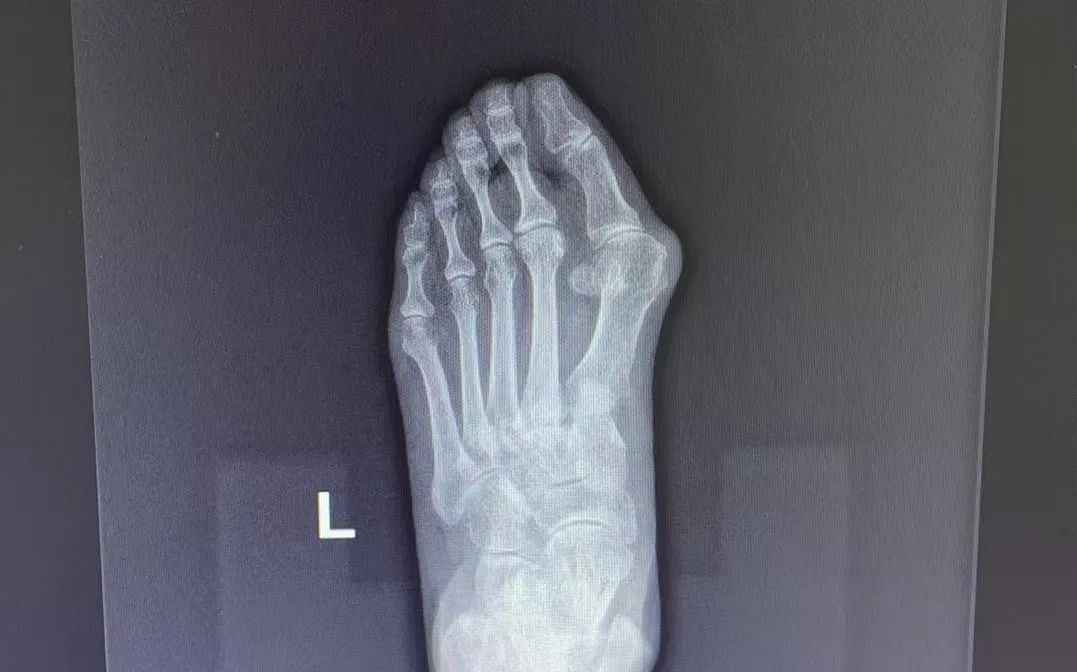

△患者手术前后比对

对于非手术干预无效或严重影响生活质量的患者,可考虑手术干预。